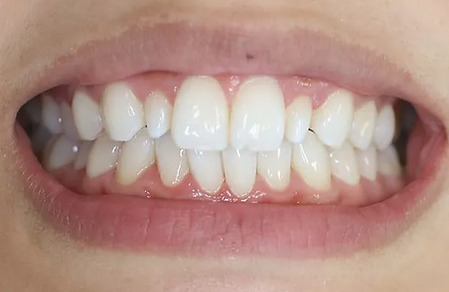

2ホワイトニング【治療例2】

治療前

治療後